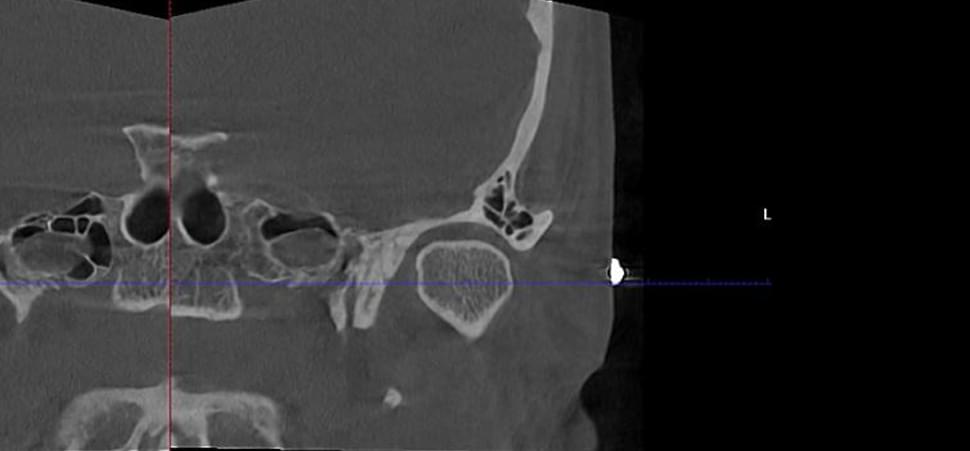

Комп'ютерна томографія

Щелепно-лицева діагностика

Опис СНЩС (суглобів)